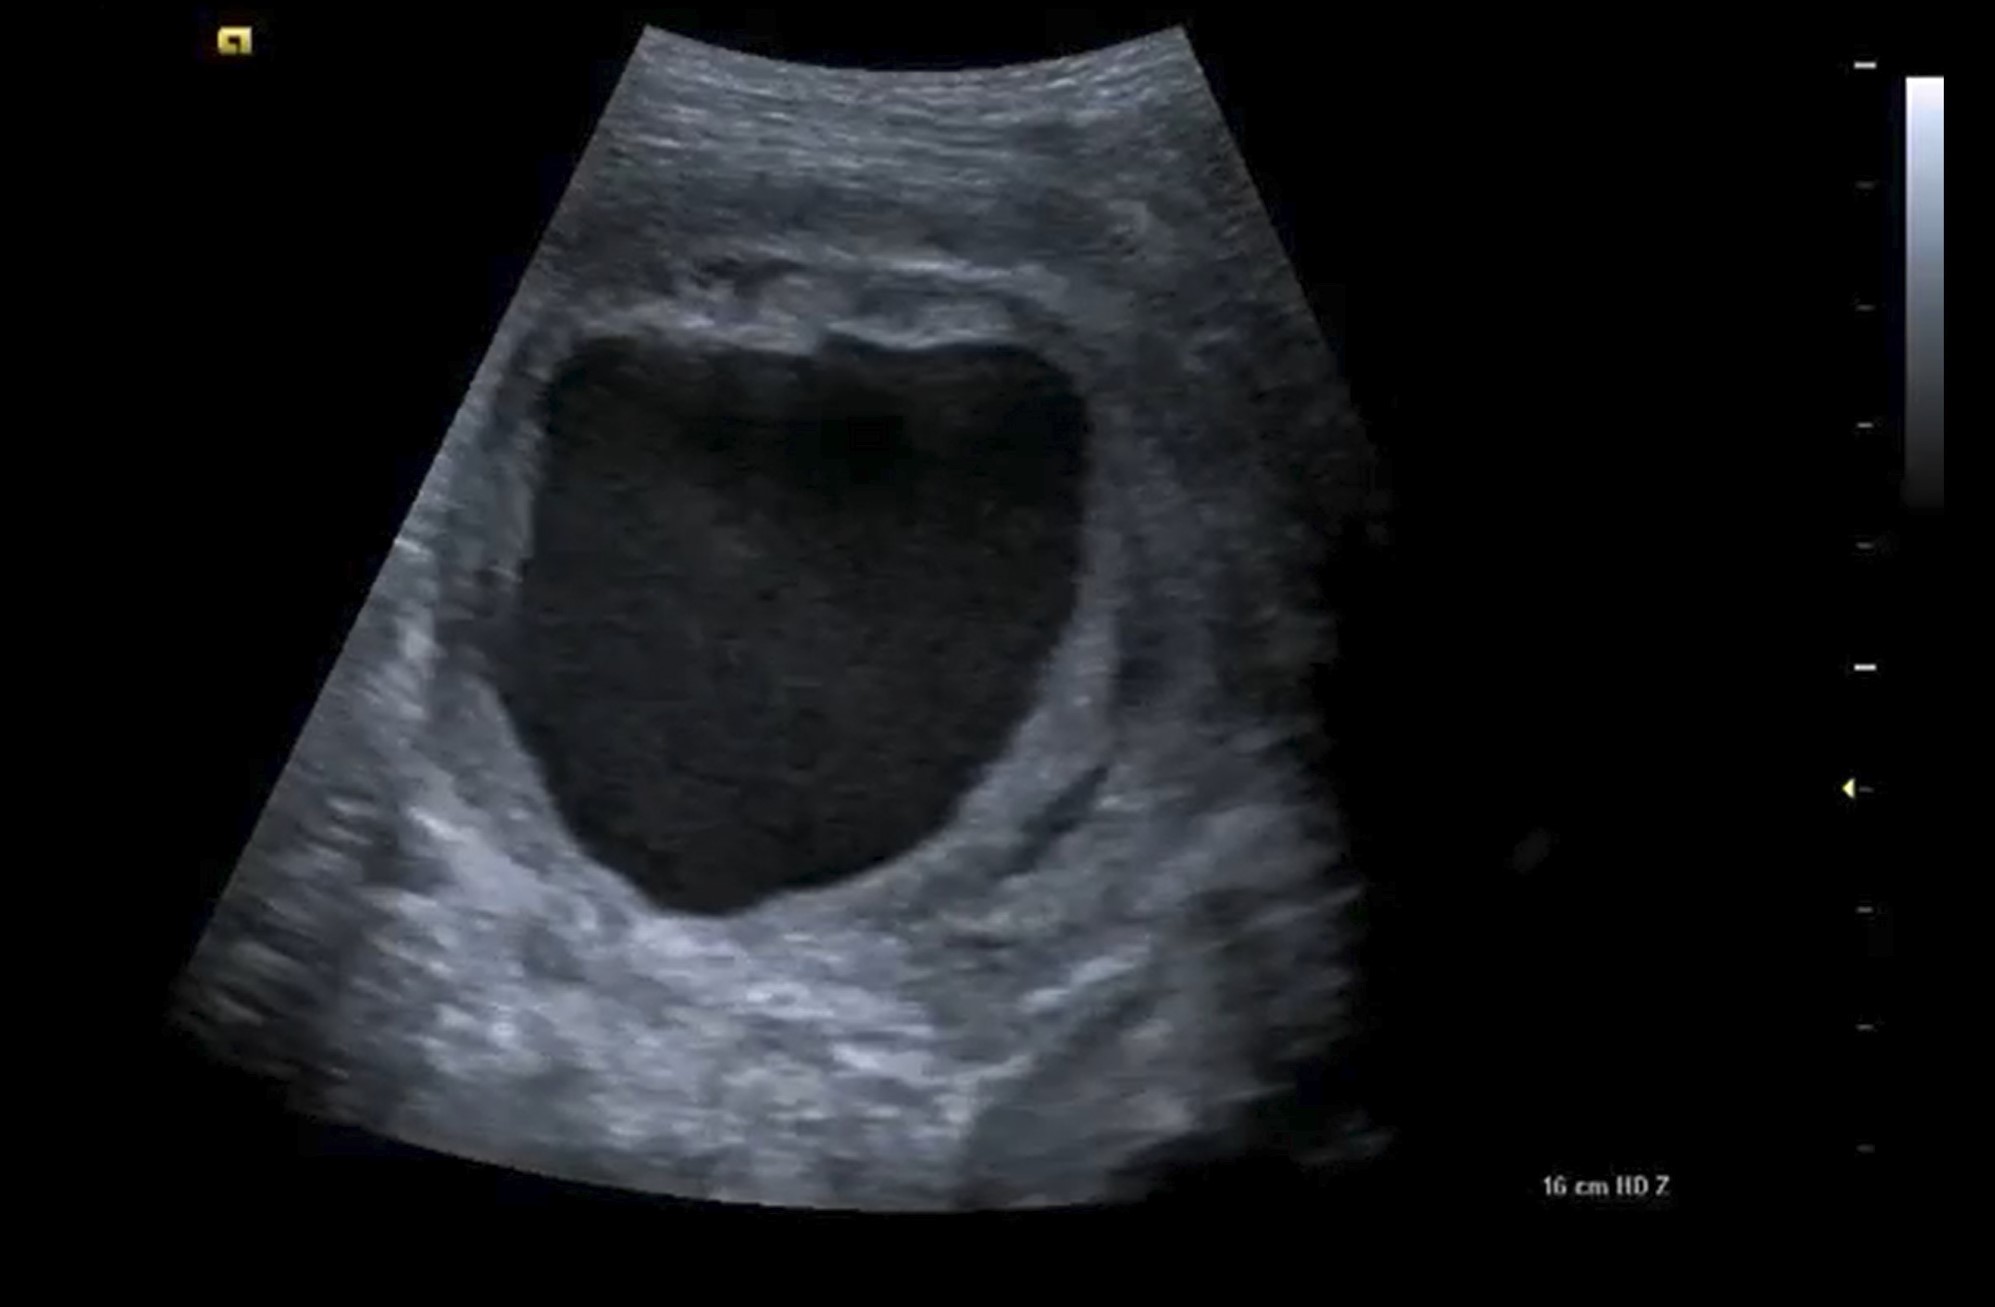

La arteria ciática persistente constituye una malformación vascular congénita excepcional, caracterizada por la permanencia anómala de este vaso embrionario que en condiciones normales involuciona para dar paso al desarrollo definitivo de la arteria femoral. Su interés radica en que presenta una marcada predisposición a desarrollar aneurismas, lo que le atribuye una importante relevancia clínica pese a su baja prevalencia. El diagnóstico puede facilitarse mediante el uso de la ecografía, ya que el signo del Yin-Yang en Eco-Doppler es un hallazgo característico.